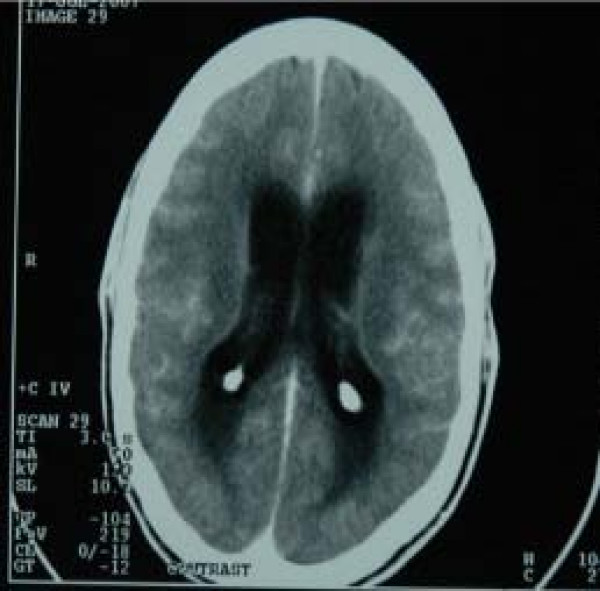

Це клінічна форма туберкульозу, при якій відбувається специфічне запальне ураження центральної нервової системи. При цьому виникає інфікування мозкових оболонок туберкульозною мікобактерією з розвитком серозного менінгіту з переважним ураженням основи головного мозку.

На відміну від багатьох інших випадків бактеріального менінгіту, туберкульозний часто важко діагностувати, адже початкові клінічні прояви, як правило, є підгострими й часто неспецифічними, а менінгеальні симптоми, як правило, не виявляються на ранній стадії захворювання. Через пізню діагностику ефективність його лікування вкрай низька, часто туберкульозний менінгіт закінчується смертю.

Хвороба починається зі слабкості, втомлюваності, зниження апетиту, сонливості, апатії. Температура тіла спочатку субфебрильна, а саме від 37,1°C до 38,0°C. Вже з перших днів проявляється головний біль, який посилюється при яскравому світлі та шумі, іноді у хворих раптово виникає блювота. Основні симптоми починаючи з п'ятого дня хвороби — з'являється гарячка, посилюється головний біль, а при подальшому розвитку хвороби виникає сплутаність свідомості. У найгіршому варіанті розвитку недугу, за відсутності специфічного лікування — кома й смерть. Прояви менінгеального синдрому відсутні у п'ятої частини хворих на туберкульозний менінгіт на початку хвороби.